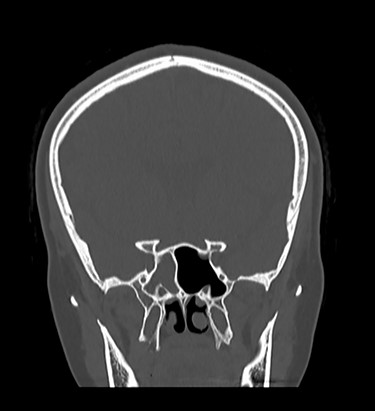

A 36-year-old female patient presented to our emergency department with fever, headache, altered level of consciousness and agitation. Patient provided history of headache and clear watery rhinorrhea from the right side of the nose after nasopharyngeal swab for COVID-19 started four months prior to her presentation. She has a significant past medical history of IIH that was evident by magnetic resonance imaging (MRI) in 2018 with empty Sella Turcica sign (Fig. 1).

Sagittal MRI of brain, T1 weighted image, showing evidence of empty Sella Turcica (arrow).